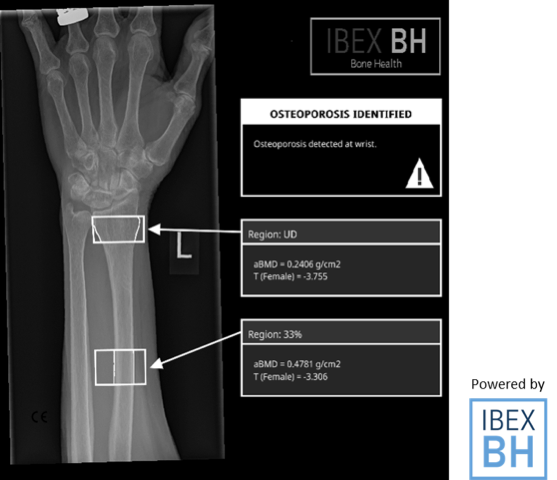

| 11:30-12:30 | Talk 2: Powerful Statistical Modelling and AI Tools for accurate, cost-effective X-ray imaging. |